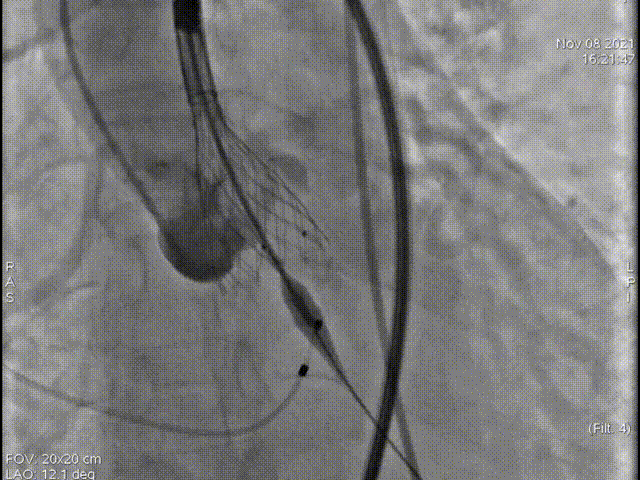

术中影像

主动脉根部造影

术中多次室颤,故当机立断,不进行预扩,直接植入L26号的VenusA-Valve瓣膜。

起始释放

第一次释放

位置稍深,选择回收,重新定位释放

第二次起始释放

第二次释放位置良好

瓣膜打折

球囊后扩

最终位置完美,无瓣周漏

术后造影及超声探查未见瓣周漏,跨瓣压差由术前70mmHg降为8mmHg,术中及术后未出现相关并发症,手术圆满完成。